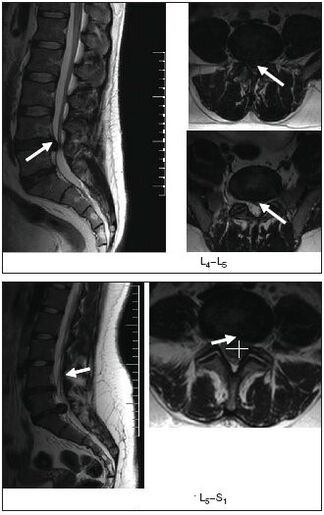

- A ressonância magnética ou a tomografia computadorizada mostrarão hérnias intervertebrais, distúrbios estruturais da coluna vertebral, problemas nos tecidos circundantes (nervos, músculos, vasos sanguíneos).